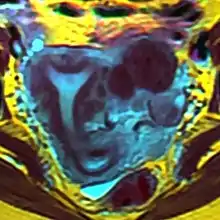

The arcuate uterus is a form of a uterine anomaly or variation where the uterine cavity displays a concave contour towards the fundus. Normally the uterine cavity is straight or convex towards the fundus on anterior-posterior imaging, but in the arcuate uterus the myometrium of the fundus dips into the cavity and may form a small septation. The distinction between an arcuate uterus and a septate uterus is not standardized.

The uterus is formed during embryogenesis by the fusion of the two Müllerian ducts. During this fusion a resorption process eliminates the partition between the two ducts to create a single cavity. This process begins caudally and advances cranially, thus an arcuate uterus represents an incomplete absorption process in the final stage.